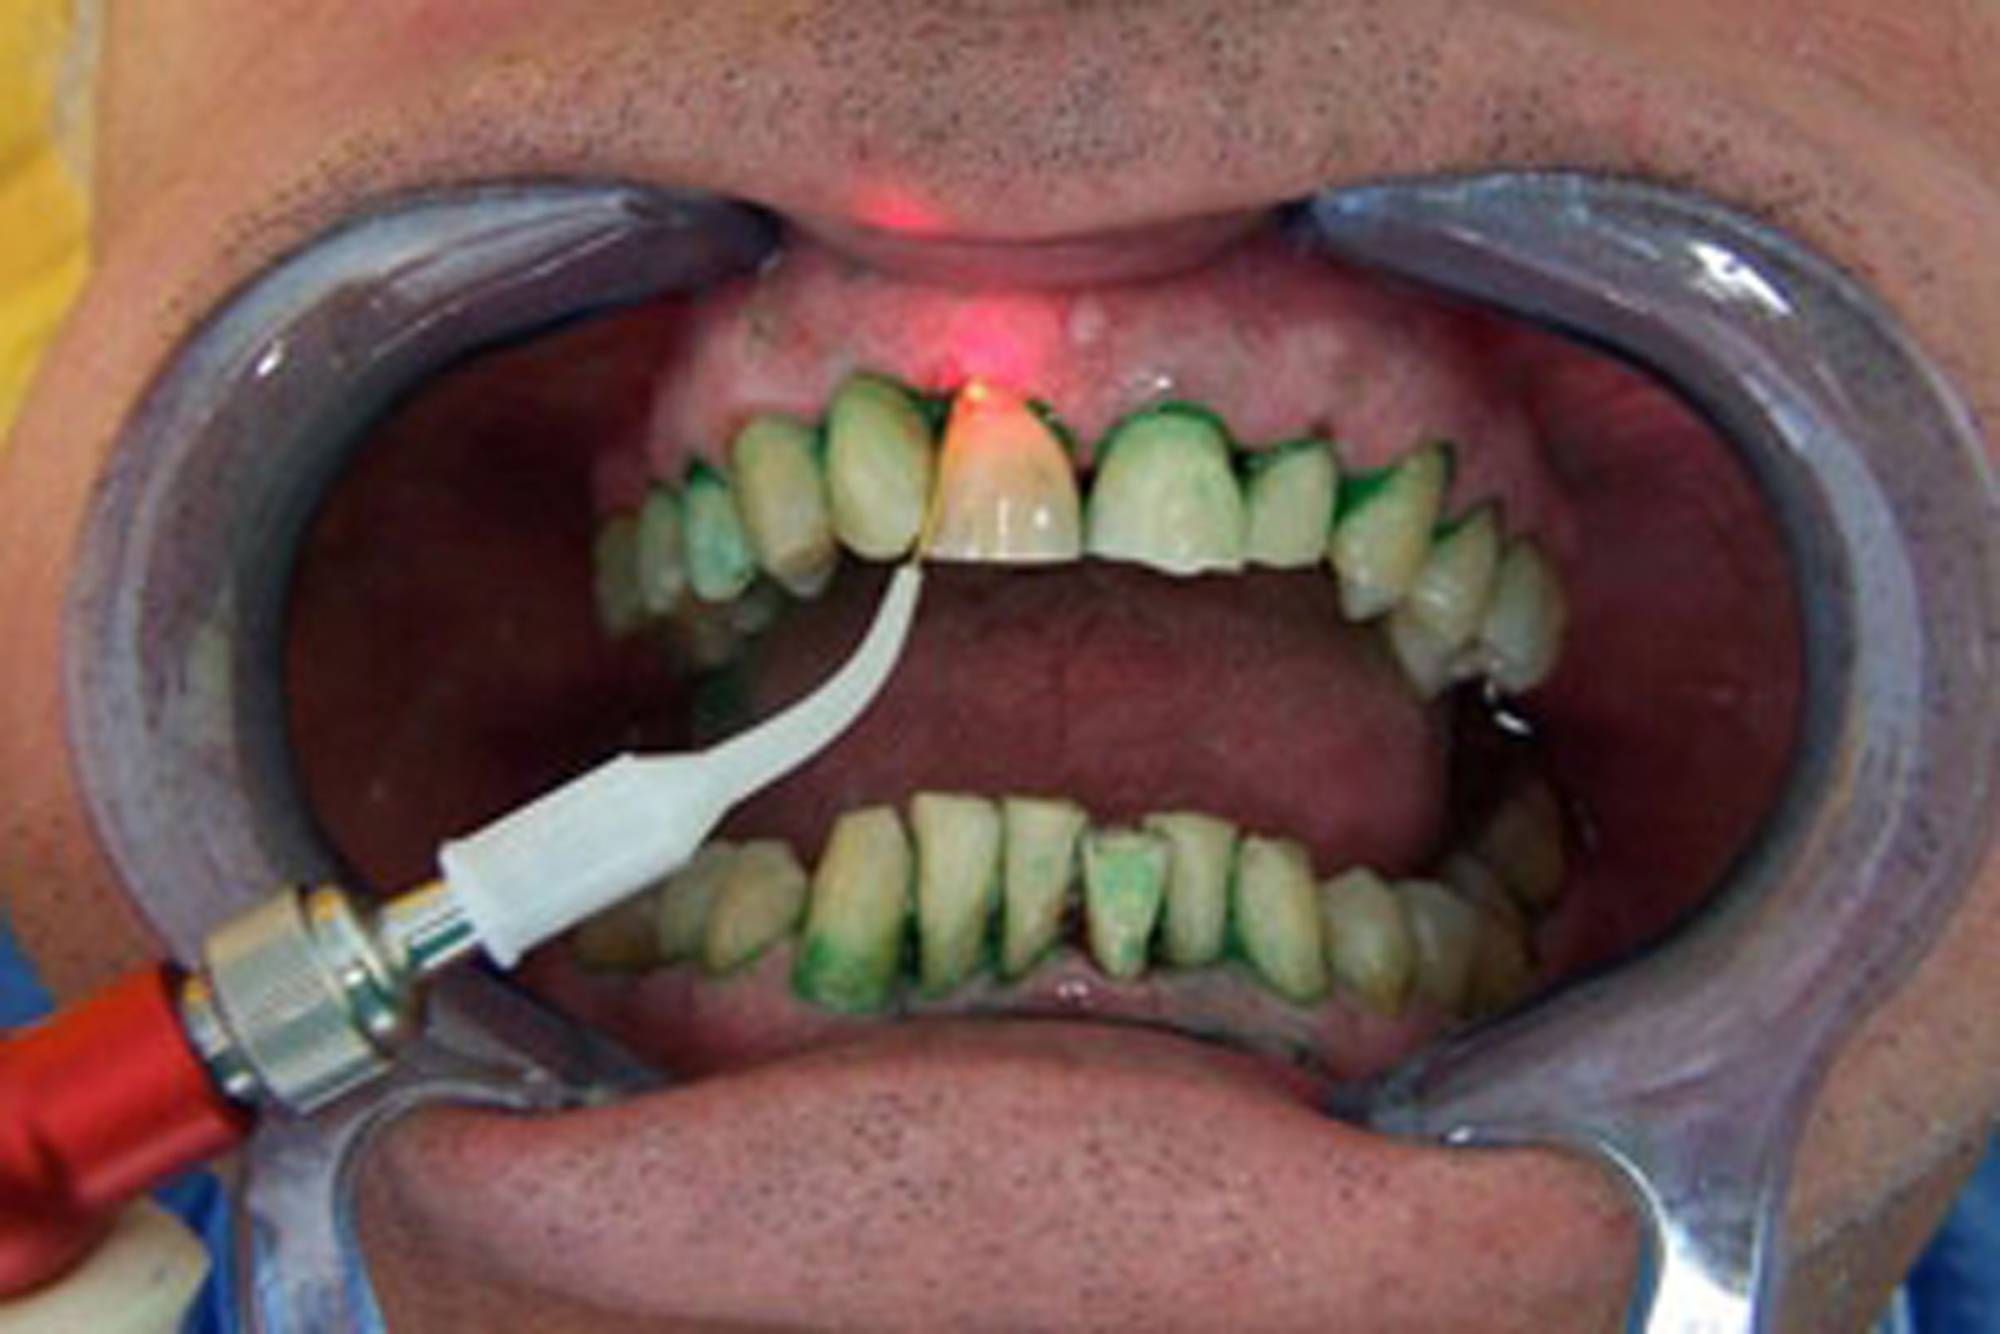

Recentemente abbiamo introdotto anche la terapia laser fotodinamica antimicrobica. Una sostanza colorante fotosensibile viene distribuita nelle tasche gengivali e si diffonde nel biofilm in cui vivono i batteri. Le molecole coloranti vengono attivate dalla luce laser che in questo modo riesce a distruggere il 99% dei batteri presenti nella tasca parodontale.